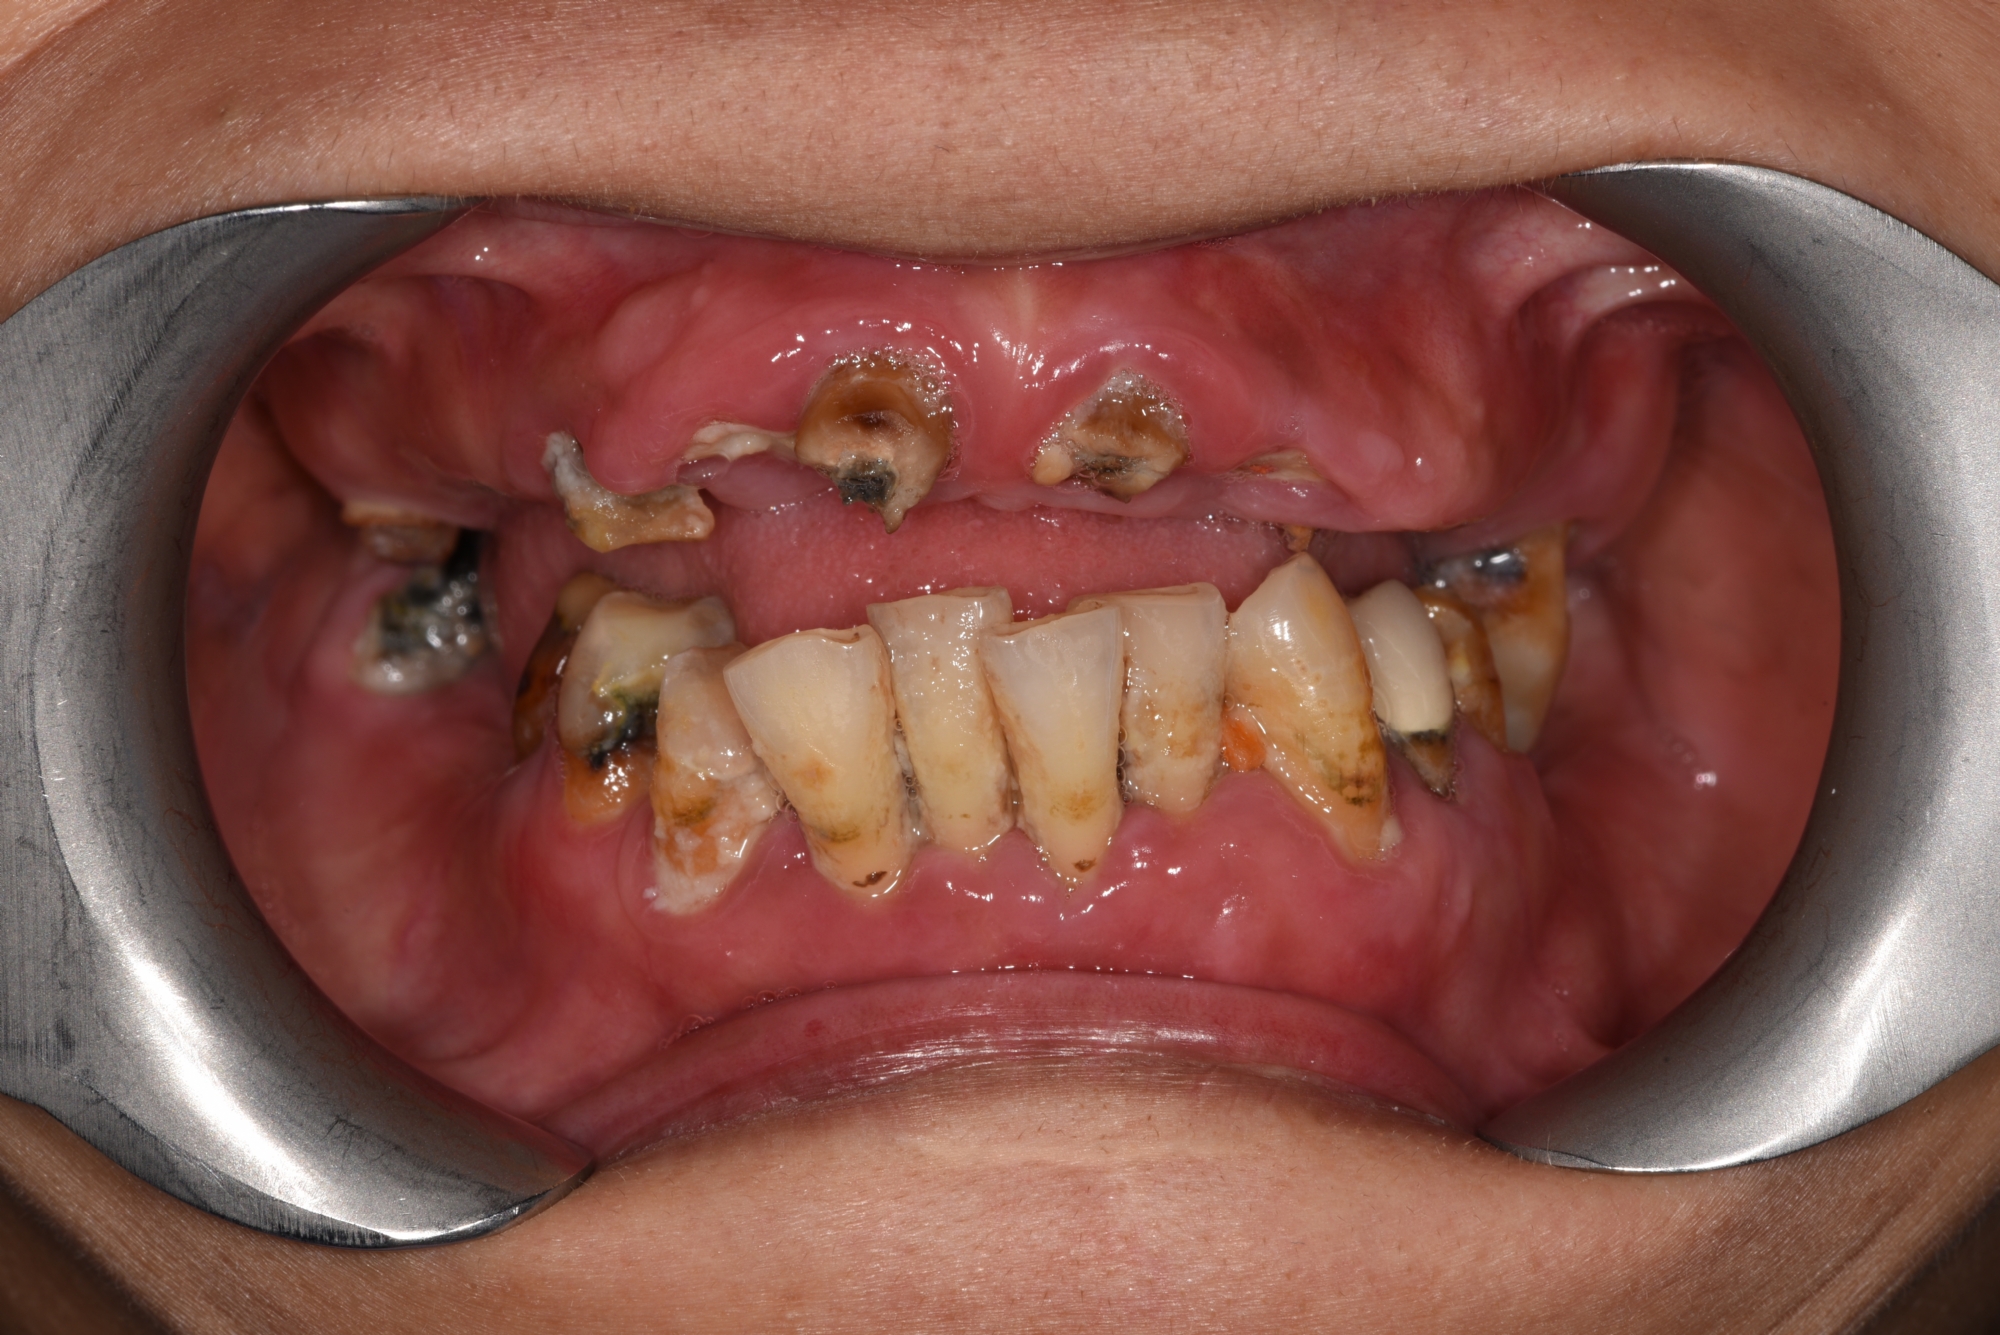

病友長期假牙有問題,某天突然掉落斷裂,經過一日全口重建固定式ALL On 4 假牙,同事朋友都沒發現她牙齒不見,只覺得隔天變得更美了